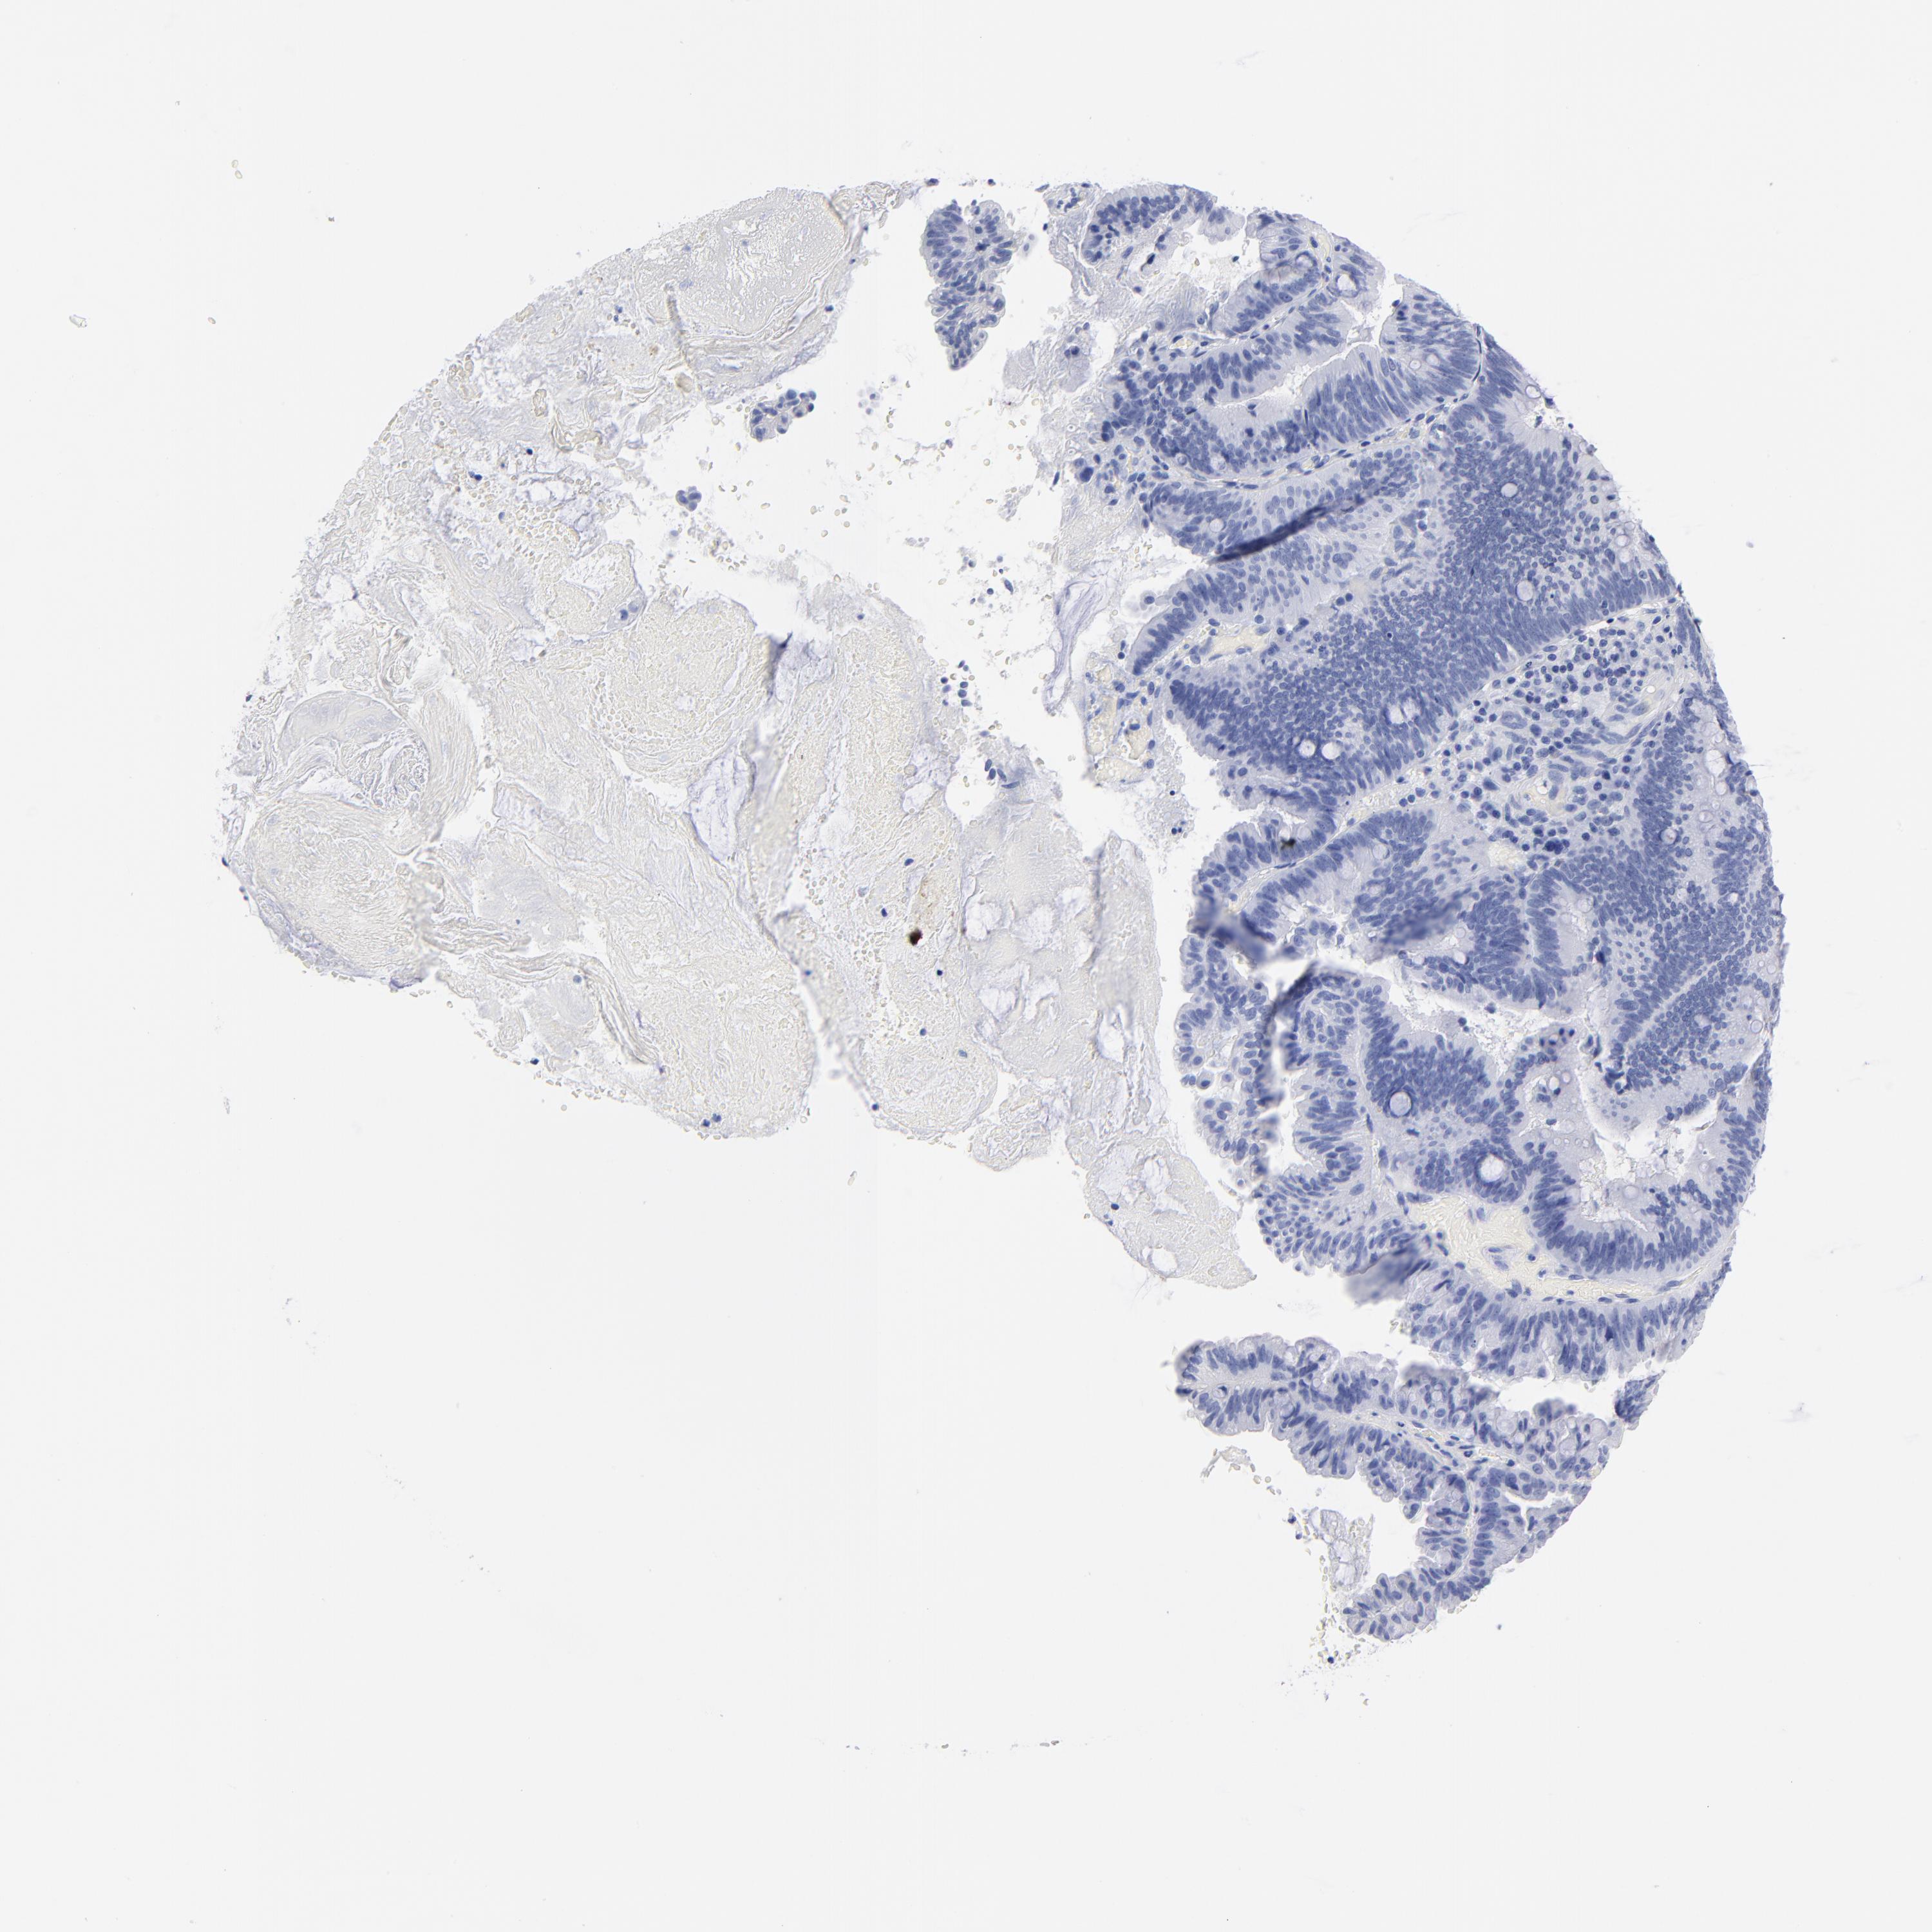

PANCREATIC CANCER - Protein expressioni

A mouse-over function shows sample information and annotation data. Click on an image to view it in a full screen mode. Samples can be filtered based on level of antibody staining by selecting one or several of the following categories: high, medium, low and not detected. The assay and annotation is described here.

Note that samples used for immunohistochemistry by the Human Protein Atlas do not correspond to samples in the TCGA dataset.

Antibody stainingi

Antibody staining in the annotated cell types in the current human tissue is reported as not detected, low, medium, or high, based on conventional immunohistochemistry profiling in selected tissues. This score is based on the combination of the staining intensity and fraction of stained cells.

Each image is clickable and will lead to virtual microscopy that enables deeper exploration of all samples and also displays staining intensity scores, fraction scores and subcellular localization as well as patient and tissue information for each sample.

Antibody HPA036174

Antibody HPA036175

Antibody CAB003695

Staining

High

Medium

Low

Not detected

Intensity

Strong

Moderate

Weak

Negative

Quantity

>75%

75%-25%

<25%

None

Location

Nuclear

Cytoplasmic/membranous

Cytoplasmic/membranous,nuclear

Adenocarcinoma, NOS

Adenocarcinoma, metastatic, NOS